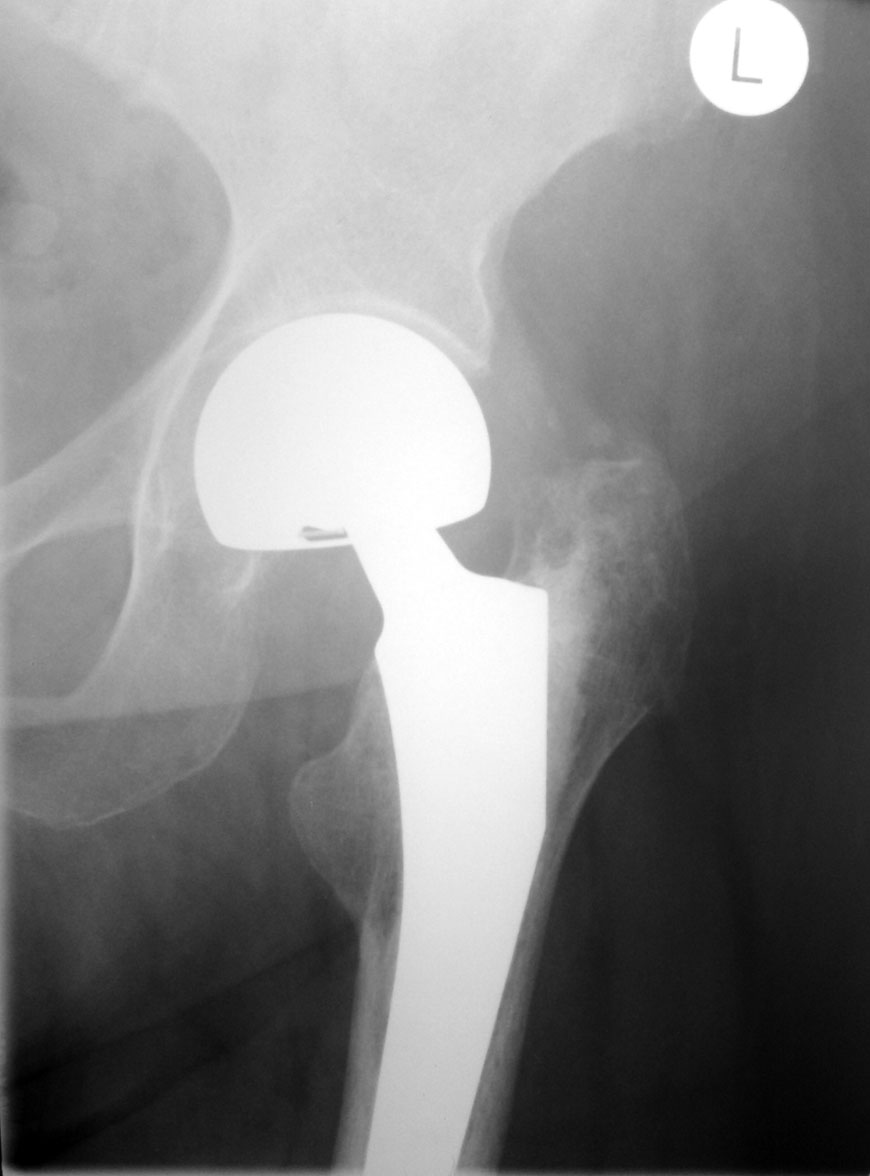

Как оценят коллеги состояние этого сустава? Возраст 77 лет, пол женский. Операция 8 мес назад.

Угол наклона чаши вертлужной впадины стремится к нулю... Расстояние от края чаши до костной основы впадины должна быть меньше 2 мм, но контур кости ровный и четкий.

Отведение вообще возможно? Протез головки бедра расположен эксцентрично, но рановато для износа полиэтилена, наверное. Нужен послеоперационный снимок для оценки динамики.

Ножка протеза беспокойства не вызывает.

По положению компонентов претензий нет. Смущает приведение в т/б суставе, но скорее всего лаборант ногу не отвел, а вообще приводяще-сгибательная контрактура у пожилых пациентов обычное дело.

Вероятно, стрелочками, которыми я просил отметить признаки биполярности протеза, следовало бы отметить контур и субхондральные слои вертлужной впадины, на которых нет признаков ятрогенной деструкции (когда впадина "вычищается" абразивом) - характерного неравномерного остеосклероза?

Признак биполярности я усматриваю со стороны основания «головки»: угадывается вложенность малой сферы в большую. Подробности по ссылке. Это только моё частное мнение  —  3D-представление и я не Источник.